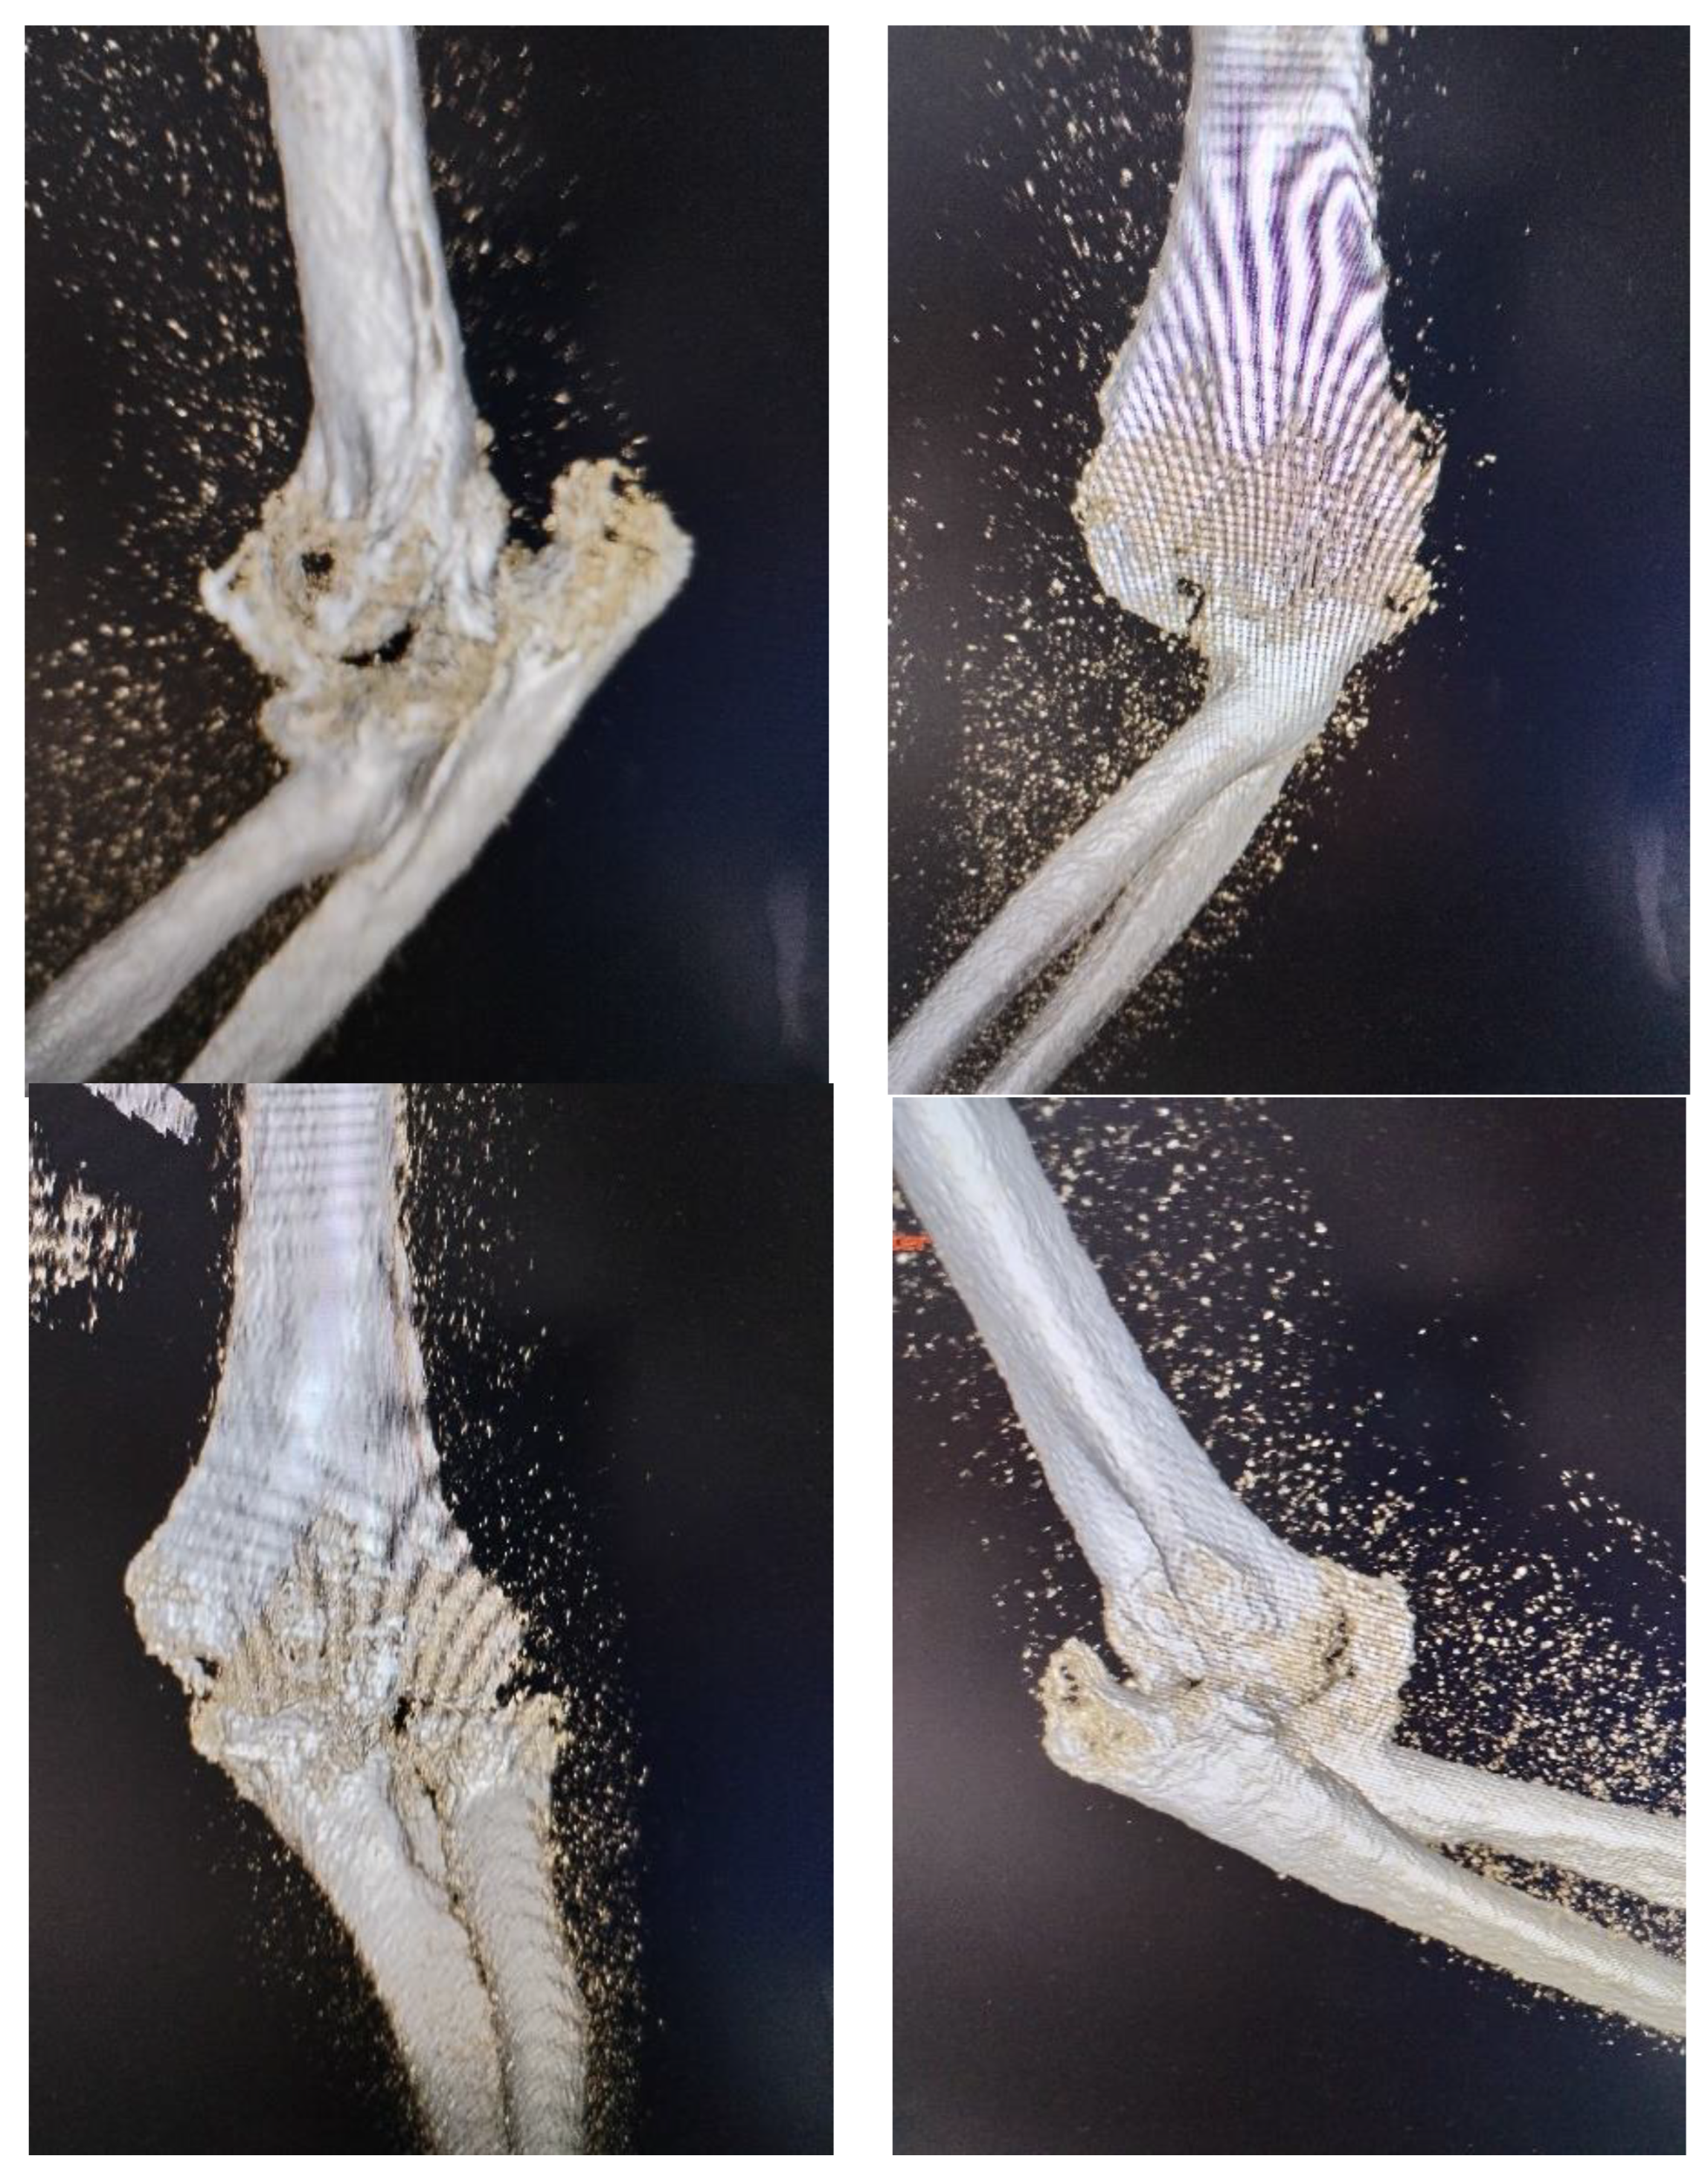

For our case we chose the two incision approach. The reason was to provide as much joint stability as possible. The patient had general anesthesia and were positioned in dorsal decubitus with the affected arm placed on the chest. This position allows exposure to the both side of elbow, medial and lateral. Tourniquet was applied on the proximal arm. On medial side was identified the ulnar nerve, who was then protected throughout surgical intervention. Its separation from the fibrous and bony tissue mass was difficult, requiring extra care to avoid intraoperative injury. Combined lateral and medial approach offered access to remove the big anterior ossification (Figure 3) and to clean posterior compartment. At the same time, the triceps insertion was preserved, which provided greater postoperative joint stability.

After all soft tissue was released from the bone (with exception of triceps insertion) and articular surface was free of any adhesions, anterior capsule was attached to the coracoid bone with two anchors, preventing posterior dislocation. The common extensors of the forearm were detached from the distal humerus, as they were retracted and obstructing both the visualization and removal of the intra-articular ossification.

The collateral ligaments were detached because of the degree of contracture and this aided joint motion. The detached ligaments were not reconstructed at the end of procedure, but reattached to the adjoining fibrous tissues to avoid excessive tension. The damaged radial head was removed and for supplementary stabilization an arthroplasty of radial head was performed. Usually we prefer osteosynthesis, but in this chronic case, the radial head was damaged and block the movement. After arthroplasty, pronation and supination was verified.

During manipulation of elbow, a small fragment of olecranon was displaced being stabilized with a screw. The elbow range of motion was about 100-120 degrees. The full extension could not be gained because of the contracture of biceps and brahial muscles. Pronation and supination were assessed with the elbow flexed at 90 degrees. They were complete.

Figure 3. a) lateral approach, b) massive heterotopic ossification.